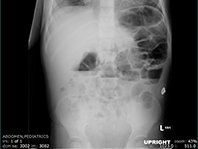

In the neonatal period this manifests as meconium ileus (MI), occurring in up to 25% of neonates with CF.11 Meconium ileus develops in utero and is characterized by thick meconium in the terminal ileum. Whereas MI may resolve on its own, it frequently presents with signs and symptoms of small bowel obstruction (SBO), such as vomiting, abdominal distention, and failure to pass meconium, and also can lead to microcolon. The patient’s X-rays will show dilated loops of bowel, sometimes with fluid levels and “soap bubbles” in the area of the meconium. Treatment is supportive with intravenous fluids and nasogastric decompression and includes surgical consultation. Hyperosmolar enema administration under fluoroscopy can dislodge meconium in 30% to 80%, although with risk of perforation it should be performed by an experienced radiologist.11 Up to 50% of cases of MI can be complicated by prenatal or segmental volvulus, ischemic necrosis, perforation, and intestinal atresia. All infants with MI should have an evaluation for CF. If the sweat test and trypsinogen are negative, infants should be referred for genetic testing.

Persistent constipation is also prevalent in this population. As a result, almost a quarter of CF patients have experienced rectal prolapse. Prolapse is rarely the initial presentation of CF, so consider other diagnoses (ie, Hirschsprung disease) first in the absence of other symptoms. However, with recurrent prolapse associated with diarrhea, evaluation for CF is warranted.1 Constipation must be differentiated from DIOS, which can present with acute right lower quadrant pain and signs and symptoms of SBO (Figure).

Distal intestinal obstruction syndrome is most common in older adolescents with a prevalence of 10% to 15.8%.13 The greatest risk factor is prior DIOS. In constipation, stool and gas accumulate gradually in the colon with or without colonic dilatation. Nonstimulant laxatives (ie, polyethylene glycol) are most commonly used for treatment of constipation and prevention of DIOS. Patients may require admission for nasogastric administration of the large volumes that are often needed (20-40 mL/kg/h) until effluent is clear. A gastrografin enema can be performed by a radiologist for treatment of DIOS.